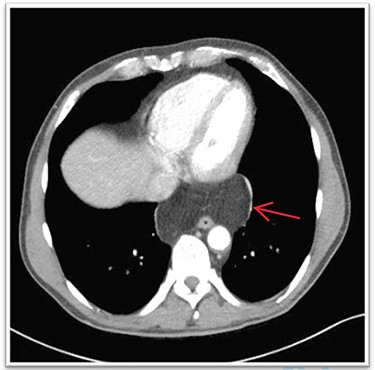

A 63-year-old male patient underwent a medical check-up due to acute bronchitis. The patient’s body mass index was 24.7 kg/m2, he was in good physical condition and no further pathological findings were revealed during clinical examination. Chest X-ray showed a retrocardiac mass (Fig. 1) and a subsequent CT scan indicated a lipomatous mass in the lower posterior mediastinum measuring 10 × 4.4 × 10.6 cm. A vascular pedicle reaching into the abdominal cavity suggested paraesophageal herniation of a large portion of the greater omentum (Fig. 2). The patient was referred to the surgical department suffering from a retrosternal feeling of pressure aggravated in supine position, with a differential diagnosis of lipomatous tumour. No symptoms of gastroesophageal reflux disease were reported, and the clinical examination showed no abnormalities. Preoperative work-up included a gastroscopy and contrast medium swallow. Endoscopy showed an axial hernia of 4 cm without further irregularities or signs of a reflux disease. Passage appeared physiological with no signs of gastroesophageal reflux and orthotopic positioning of the oesophagogastric junction.

The diagnostic approach for a mediastinal mass involves detailed history-taking, physical examination, laboratory examination and imaging studies. Commonly, a chest and abdominal CT scan with intravenous contrast agent is recommended to define the herniated structures. In the present case, CT showed a lipomatous mass and a vascular pedicle reaching into the abdominal cavity which was indicative for a PEH. Radiologically visualised continuity of the herniated structure above and below the diaphragm can be a sign of either lipomatous tumour or paraesophageal omental herniation [4]. In this case, the vessel was indicative of being the gastroepiploic artery, which is the supplying vessel of the greater omentum. In some cases, only a CT-guided tissue biopsy or diagnostic laparoscopy will result in a definitive diagnosis [5, 6]. Surgical management is indicated in symptomatic patients in order to prevent complications such as intestinal obstruction, strangulation or perforation [3].